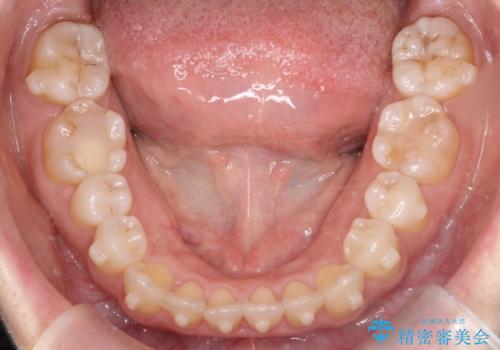

【開咬】笑った時の見た目を改善したい。

- 重度の開咬でしたがインビザラインで適切に治療計画を立て、きれいに仕上がりました。

インビザラインは開咬の治療に向いています。